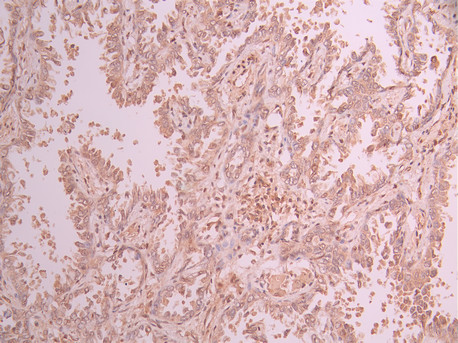

• IHC image of CSB-RA145805A0HU diluted at 1:100 and staining in paraffin-embedded human lung cancer performed on a Leica BondTM system. After dewaxing and hydration, antigen retrieval was mediated by high pressure in a citrate buffer (pH 6.0). Section was blocked with 10% normal goat serum 30min at RT. Then primary antibody (1% BSA) was incubated at 4°C overnight. The primary is detected by a Goat anti-rabbit polymer IgG labeled by HRP and visualized using 0.05% DAB.